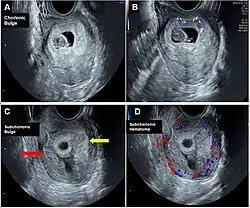

Chorionic bump is a rare medical condition defined as an irregular, convex bulge or protrusion from the choriodecidual surface into the gestational sac.[1][2] It is medically defined as a separate entity from a chorionic hematoma.[3]

Identification of a chorionic bump in early first trimester pregnancy represents a significant risk factor for pregnancy loss, given a live birth rate of less than 50%.[4] The incidence rate for chorionic bump is estimated to be between 1.5 and 7 per 1000 pregnancies.[3]